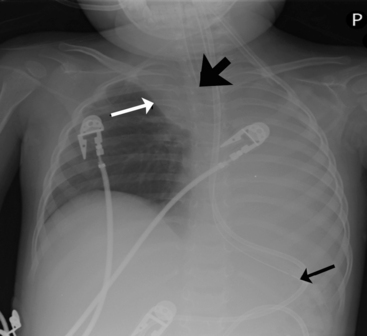

A pneumothorax will produce an air-tissue interface in the pleural cavity because the pneumothorax contains only air with no pulmonary vascular markings, whereas the lung contains air, tissues, and vessels. The presence of a significant pneumothorax will cause partial or complete collapse of the adjacent (ipsilateral) lung. Note that free pleural air will accumulate in the highest portions of the chest so that the location of the air is influenced by the patient’s position when the X-ray is obtained. In an upright film, free pleural air is typically observed above the apex of the lung, whereas in a supine film the air may accumulate along the anterior and lateral aspects of the lung and along the diaphragm (Fig. 10-7).

image

Fig. 10-7 Tension pneumothorax. This film was obtained as part of a routine daily chest radiograph to monitor for endotracheal tube placement in this 18-year-old male with methicillin-resistant Staphylococcus aureus necrotizing fascitis. This is a supine AP film that demonstrates near total atelectasis of the right lung. The pneumothorax is visible along the inferior and lateral aspects of the right chest, with a shift of the cardiac silhouette to the left. There is clear visualization of the lung-air interface (arrows) seen along the lateral and inferior margins of the right lung. This is a tension pneumothorax because the mediastinum is markedly shifted and the right hemidiaphragm is flattened out of the field of view.